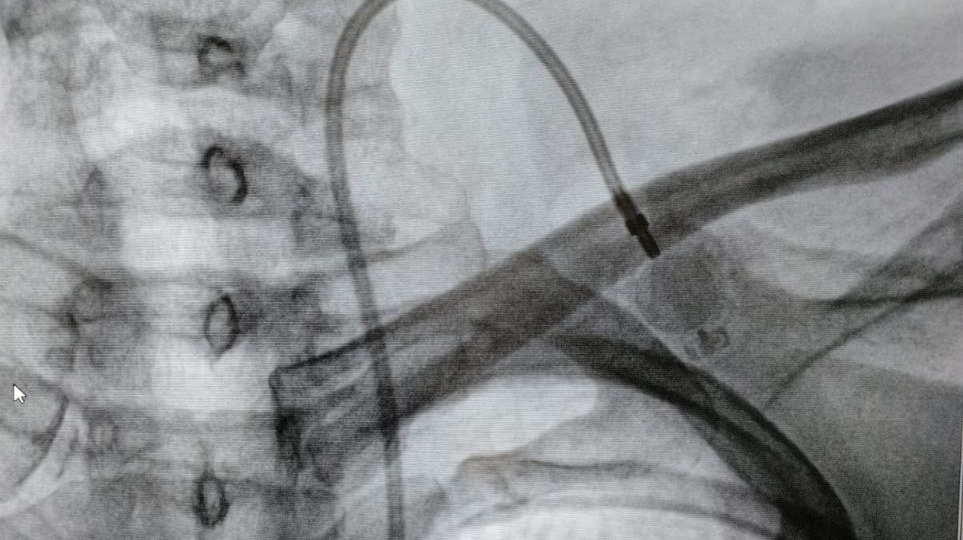

Точно в цель: в Саратовском медицинском центре ФМБА России освоили установку порт-систем для химиотерапии

В Саратовском медицинском центре ФМБА России успешно внедрили современную методику подкожной имплантации порт-систем. Эти устройства предназначены для длительной и безопасной химиотерапии, парентерального питания и сложного лечения. Установку выполняет заведующий отделением сосудистой хирургии Виктор Анатольевич Егоров. Что такое порт-система? Это небольшой титановый резервуар с силиконовой мембраной, который имплантируют под кожу в подключичную область. К нему подводят катетер, который устанавливают в крупную магистральную вену. Система полностью скрыта под кожей, что позволяет пациентам вести привычный образ жизни — принимать душ, плавать и заниматься спортом. Ключевые преимущества методики: · Безопасность и комфорт. Исключается риск повреждения периферических вен агрессивными препаратами. Лекарство поступает сразу в крупный сосуд, где быстро разбавляется кровью, что снижает риск воспалений и раздражений. · Надёжность. Система избавляет от необходимости многократных пункций, минимизи